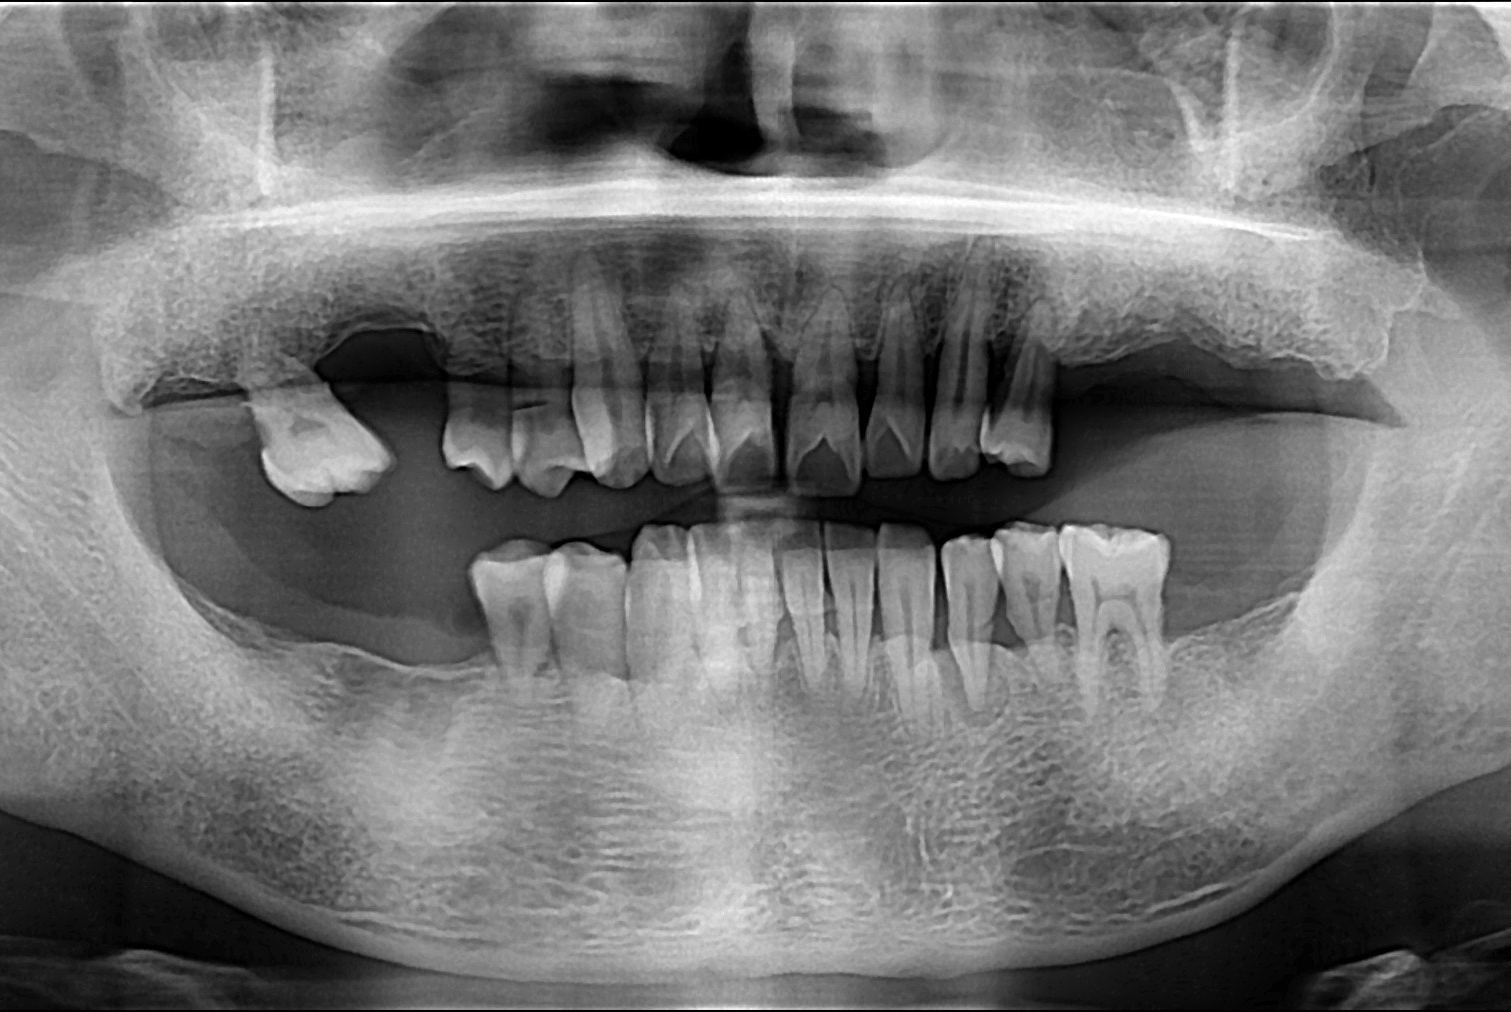

치료전 : 2018-08-30

세종치과는 많은 환자와 다양한 케이스를 바탕으로 항상 편안한 임플란트 수술을 제공하고자 노력하고,

오래동안 튼튼히 쓸 수 있는 임플란트 수술을 가장 큰 목표로 삼고 있습니다